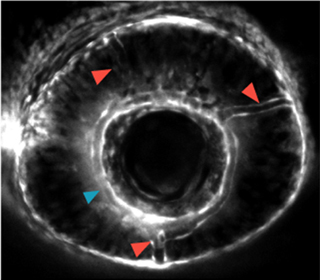

この遺伝子は新規であるため機能情報が無く、本当に血管の形成にかかわる遺伝子であるかどうか分かりませんでした。そこで、ゼブラフィッシュでこの遺伝子の発現を抑制してみることにしました。発達期にこの遺伝子の発現を抑制すると、頭蓋内の眼動脈や脊椎動脈の分岐の異常が出ることが分かりました。特に、頭蓋内の眼動脈の分枝異常は過去に報告されたことのない非常に興味深いものでした(図1)。血管形成に重要な新たな遺伝子であることが分かりました。

正常 |  mysterin抑制 |

- 図1 ゼブラフィッシュにおけるmysterin抑制による眼動脈分枝異常

mysterinを抑制すると、分枝する眼動脈(赤矢印)の数が増えるという異常が起こる